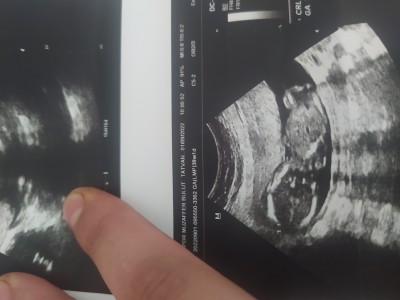

Kızlar merhaba ben 16 haftalıkken gittim doktor erkeğe benziyor dedi şimdide 21 inci haftamdayim dün tekrar başka doktora gittim kıza benzettim dedi net bişey söylemedi kafam çok karıştı ultrason fotoğrafi var 16. Haftaya ait bakar misiniz

image

Gebelik haftası 21